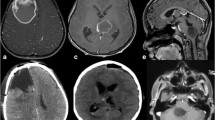

Histological features such as necrosis (palisading/geographical/ischemia-like focal), vascular endothelial cell proliferation, and microcalcification were considered as positive if observed in the tissues. The presence of mitosis was counted in 10 high power fields (hpf). Furthermore, the tissues were considered as positive for nuclear pleomorphism, epithelioid and small cell morphology, primitive neuroectodermal tumor (PNET)-like and microcystic areas, gemistocytic appearance with perivascular arrangement of the tumor cells when these characteristics were observed in more than 10% of the tumor area. Piloid and myxoid morphology, multinucleated giant cells and oligodendroglioma-like morphology were graded as 0 if absent or present in less than 10% of the tumor area, +1 when present in 10–30% of the tumor area, and +2 when present in more than 30% of the tumor area (Fig. 1a–c, e, h, i, k, l).

Morphological and immunohistochemical features of pHGGs. a Geographical necrosis (arrows) (H&E, ×200). b Palisading necrosis (arrows) (H&E, ×200). c VEP (H&E, ×200). d–f H3K27M-mutated glioma with multinucleated giant cells. d Immunohistochemical expression of H3K27M mutant protein in tumor cells (arrows indicate endothelial cells) (H3K27M, ×400). e Pleomorphic and multinucleated tumor cells (arrows) (H&E, ×400). f Loss of immunohistochemical expression of ATRX in tumor cells (arrows indicate endothelial cells) (ATRX, ×400). g–h H3K27M-mutated glioma with pilocytic like morphology g Immunohistochemical expression of H3K27M mutant protein in tumor cells (arrows indicate endothelial cells) (H3K27M, ×400). h Pilocytic morphology and focal-ischemia-like necrosis (arrows) in tumor cells (H&E, ×200). i Myxoid morphology (H&E, ×400). j–k H3K27M-mutated glioma with oligodendroglioma-like appearance. j Immunohistochemical expression of H3K27M mutant protein in tumor cells (arrows indicate endothelial cells) (H3K27M, ×400). k Oligodendroglioma-like morphology (H&E, ×400). l Small cell morphology (H&E, ×400). m Immunohistochemical expression of IDH1 mutant protein in tumor cells (arrows indicate endothelial cells) (IDH1, ×400). n Immunohistochemical expression of BRAF V600E mutant protein in tumor cells (BRAF V600E, ×400). o The p53 immunoreactivity (graded as +3) in tumor cells (p53, ×400). Scale bar represent 200 μm ×200, 100 μm ×400 objectives

Immunostaining for H3K27M was evaluated according to the nuclear staining of the tumor cells. The presence of nuclear staining for H3K27M mutant protein in the tumor cells but not in the endothelial cells or normal brain was considered as evidence of mutation [14, 15]. Due to the difficulty in distinguishing non-specific cytoplasmic immunoreactivity in microglial/inflammatory cells, and necrosis, tumors that did not contain these areas were selected for evaluation by immunostaining. For ATRX, complete loss of nuclear staining in tumor cells with retained expression in the non-tumor cells was considered as loss of nuclear protein expression. For both IDH1 and BRAF V600E, diffuse cytoplasmic immunoreactivity was considered as evidence of mutation [19, 20]. p53 immunoreactivity was determined by approximation of the number of positively stained tumor cell nuclei in hpf (×400). p53 immunoreactivity was graded as 0 when no staining of the nuclei was observed; +1 when less than 10% of the nuclei were stained; +2 when 10–50% of the nuclei were stained; and +3 when more than 51% of the tumor cells nuclei were stained [21]. The Ki-67 proliferative index was expressed in percentage by determining the number of immunopositive nuclei calculated by manually counting 1000 nuclei in the area of maximal staining for each tumor in hpf (×400) [21] (Fig. 1d, f, g, j, m–o).